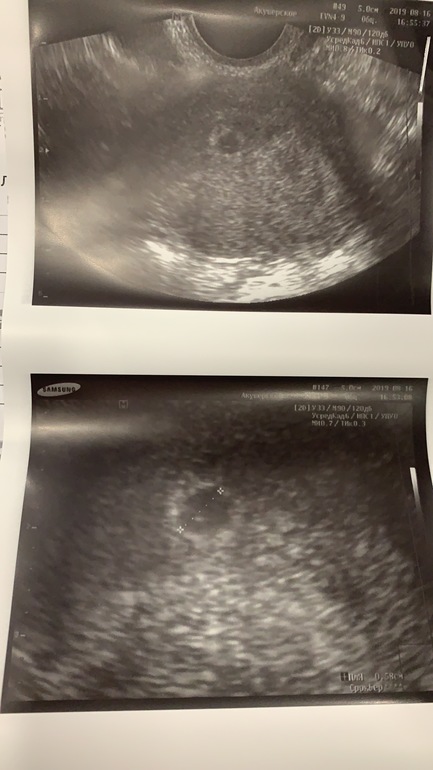

17 дпп УЗИ 1 ПЯ в матке, 5,8 на 5,6 мм,

желточный мешочек 2 мм

УЗИ 26дпп - 1 ПЯ, есть сердцебиение

19дпп - ПЯ в матке

22дпп - сб+

24 дпп 1 ПЯ в матке, ЖМ 3.3 мм

УЗИ - 1 пя

Узи на 22 дпп : 2 п.я в матке , в одном пульсирует сердечко.

УЗИ на 16 ДПП: 2 ПЯ , в одном из них ЖМ.